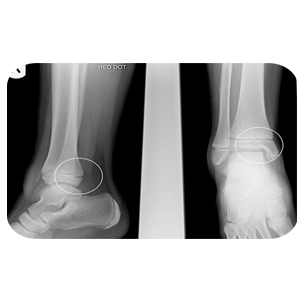

Units of the Department of Forensic Medicine and Clinical Toxicology Head of the Department's Message Services Units Academic Staff Course Description The department has the following devices and samples: